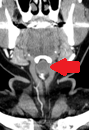

Thyroglossal duct cysts. Neck MRI – Detailed imaging of the cyst. Courtesy Dr. V. Penopoulos.